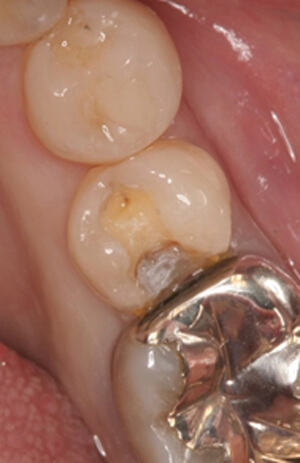

ダイレクトボンディング症例2

詰め物が取れた

術前

詰め物が取れてしまい、しみるためダイレクトボンディング治療を希望されました

ダイレクトボンディング治療後

術後